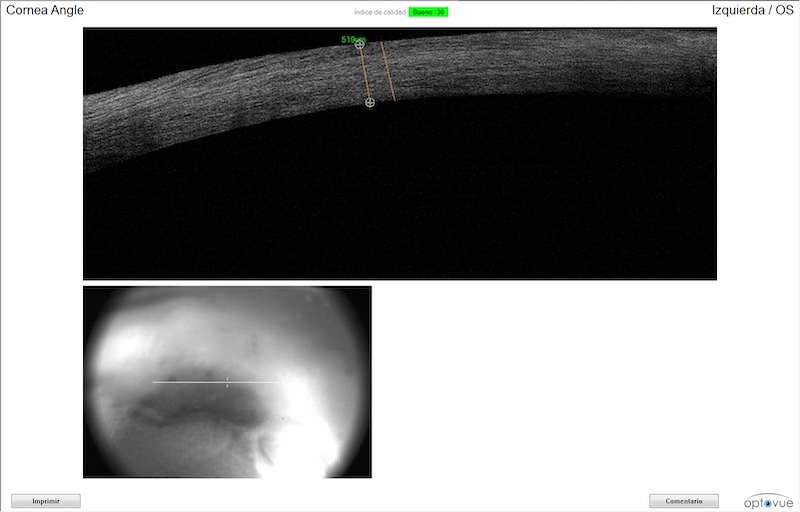

Fue necesario realizar una tomografía de coherencia óptica corneal (OCT) para evaluar la profundidad de la úlcera y una citología para determinar con mayor precisión el tipo de infección que presentaba.